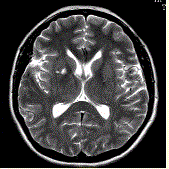

问题 男性,55岁。临床偶尔头晕,无高血压,糖尿病病史。MRI显示如下图。 关于血管周围间隙,描述错误的是

选项 A.单层或多层柔脑膜包绕 B.邻近脑实质可见胶质增生 C.临床无症状 D.3T常见,各个年龄均可见 E.位于基底节区(前联合附近),其他常见位置:中脑,白质深部

答案 B